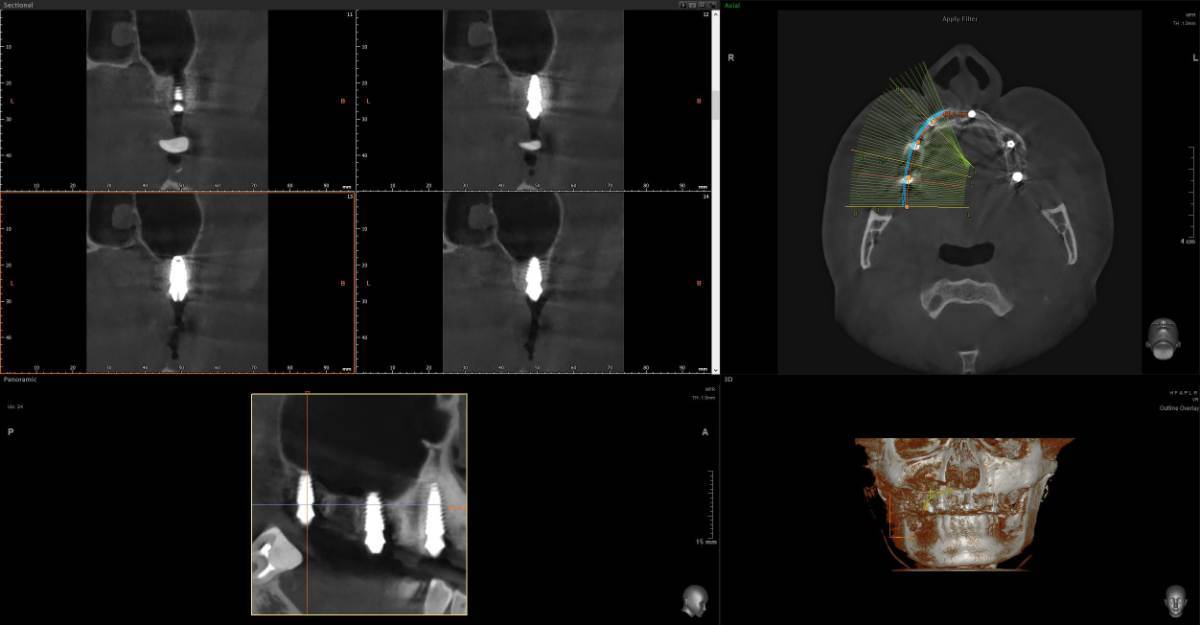

Добрый день. Зубы проблемные с детства очень сильно Полтора-два года назад предварительно удалось спасти не спасаемое, 26 и 27, по крайней мере по нескольких кт перидически, неплохой регресс и заживление костной ткани, даже в области 26 где было большое поражение фуркации, сейчас намного меньше, они не болят уже почти год, до этого очень долго болели даже после качественного лечения и врачи прогнозов не давали конечно же между 24-26 (25 нет уже лет 10) стоит адегизивный бабочка, уже не в самом лучшем состоянии, вернее зубы 24 26 не в очень хорошем, так вот я хотел снять бабочку и одеть на 24-26 металлокерамику, во рту есть несколько металлокерамик единичных, на 3 еще не ставил Есть вариант, и я послушал разных докторов, что можно было бы например 24 просто сделать реставрацию качественно, 26 там без вариантов покрыть коронкой единичной, а 25 имплантат, но я пока избегаю всего так сказать инвазивного, хотя бы еще полтора-два года, с начала 2024 и по середину 2025 болел очень тяжело, Лонг ковидом, это страшное явление которое врагу не пожелаю, возможно даже кто помнит мои темы что я у себя предполагал сепсис, вот именно у меня был он не в виде усталости какой и тд, что чаще всего, а в форме выраженного иммунодефицита + легкого но стойкого системного воспаления , по типу аутоиммунных реакций, в общем не будем вдаваться в эту тему, к тому же она не изучена еще, все только предстоит, спасибо лишь тем докторам-интузиастам, которые просто из спортивного интереса не забросили эту тему и занимаются исследованиями, при разных НИИ, в итоге они меня спасли, помогли определенные противовирусные на длительной основе поставить меня на ноги, что еще раз и том числе мой пример подтверждает вирусный генез Лонга, 1,5 жизни просто выпало у меня Ладно, я далеко ушел уже от темы, я к тому, что более современно наверное считается имплантат и 24 и 26 по отдельности, но повторюсь я боюсь пока лишних инвазивных процедур. Подскажите пожалуйста, каковы минусы моста с металлокерамики на 3 зуба, по каким причинам это считается прошлый век, и какие нюансы меня могут ждать ? Даже если те зубы я рано или поздно потеряю, но даже 3-4 года выиграть еще перед имплантацией, это все равно выигрыш Возможно я думал тот же мост на 3 но из циркония, но тоже не знаю, зубы те хоть и с положительной динамикой но сколько они еще простоят, а цирконий как никак в 2 раза дороже металлокерамики, но если лучше его, тогда рассмотрю -